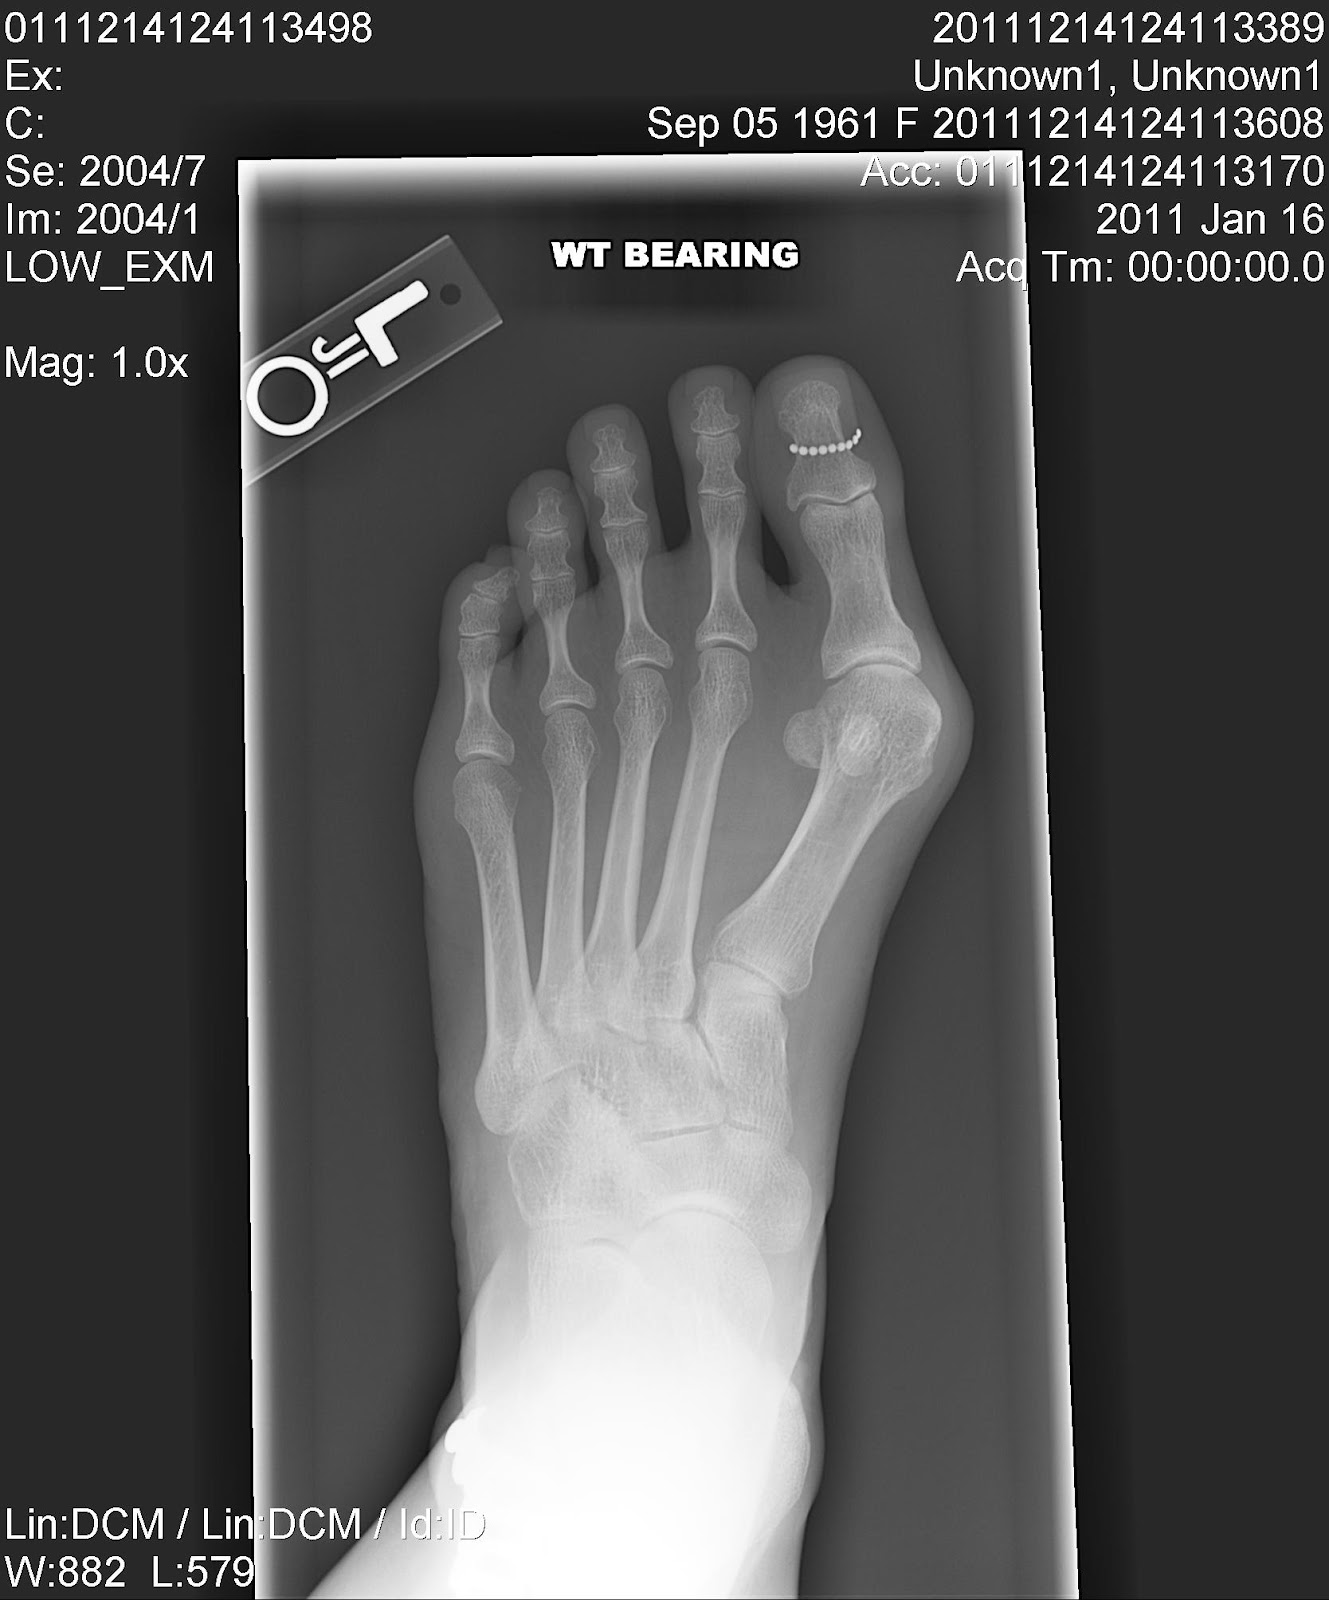

But the reason we came to Bumrungrad was for my feet, those ugly feet. After my delicious lunch I was off to the Orthopedic surgeon. He took a look at my feet, had me go to X-ray and then we talked about the options. He was very knowledgable, answered all my questions and put me quite at ease. Because doctors know you are visiting, they are able to schedule follow on appointments right away. He arranged his schedule so I can have my surgery tomorrow at 9pm. I'll spend one night in the hospital with three follow on appointments before I leave in two weeks.

We're heading out early in the morning via Qatar Airways Kuwait – Doha, Qatar – Bangkok. But before we get on the plane, I want to show you the BEFORE pictures. Warning! These photos may be disturbing.

Yes, the bones in those feet are meant to be straight. If all goes well, in a week or so they will be.

Three days after surgery the big reveal...oh my gosh...that is ugly. As you can see from the photos the doctor did two incisions per foot. The one between my toes was to release the ligaments and tendons. The larger one on the outside of the feet he cut out some of the bunion and put in a screw or two to straighten the great toe. When he talked to me after the surgery he said the tendons were very tight so the wrapping will be very important.